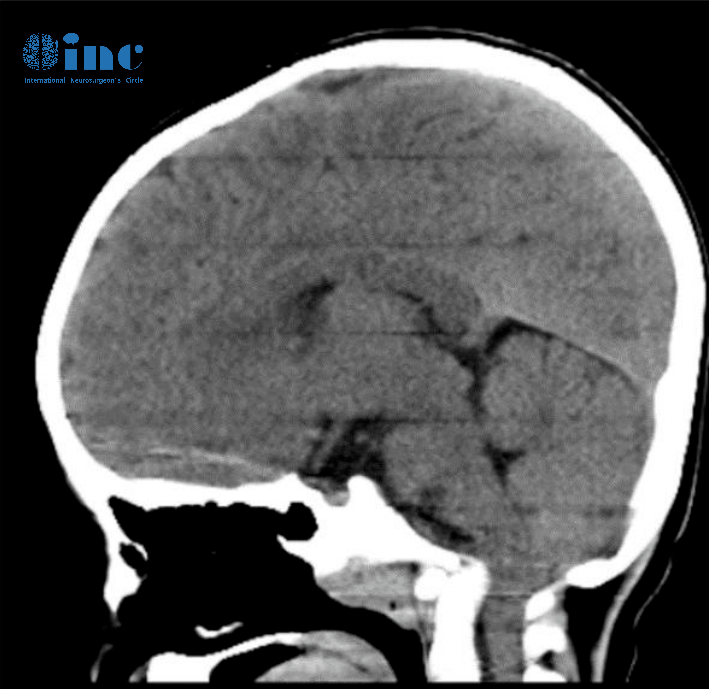

CT重建提示颅脑比例失调,这是因为大脑凸面的蛛网膜下腔体积减小,小脑蚓部向上迁移,以及与小脑中度过度生长相关的小脑幕的向上移位。

脊髓空洞症的病因多种多样,从先天性畸形到感染或脊柱肿瘤。在您们孩子的病例中,我们可以假设颅脑比例失调,因为大脑占据了全部的颅内空间,小脑很大,导致扁桃体和蚓部向下移位,并阻塞头颅和脊柱之间液体的正常流动,反之亦然。儿童脊髓空洞症的常见原因之一是终丝增厚,终丝是连接脊髓末端和骶骨的韧带,这可能导致脊髓牵拉并引起向下移位。这在您孩子的病例中并不明显。然而,孩子俯卧位的对照核磁可能有助于进一步排除这种可能性。